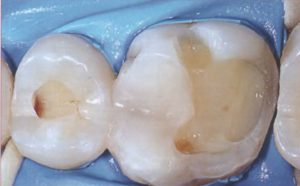

Самая распространенная болезнь полости рта – кариес. Им страдает более половины населения Земли. Возникновение и развитие патологического процесса приводит к повреждению эмали. Несвоевременное лечение кариеса разрушает твердые ткани окончательно. Для большей наглядности обратите внимание на фото пораженных зубов в сравнении со здоровыми.

Кариес на передних зубах доставляет особенный дискомфорт (резец болит, остро «реагируя» на температурные изменения), а также создает значительные эстетические неудобства (см. фото кариеса выше). Благодаря современным методам лечения остановить заболевание и кариозные изменения, вернув здоровую улыбку, можно за один прием.

Виды кариеса классифицируются в зависимости от степени поражения зуба, глубины кариозных полостей, их локализации. Этапы развития болезни с фото-иллюстрацией:

Фото демонстрирует, как выглядит кариес в различной стадии формирования. В зависимости от глубины полости гниения, различают поверхностное, среднее или глубокое кариозное поражение.

Фото — Стадия пятна Средний Глубокий кариес